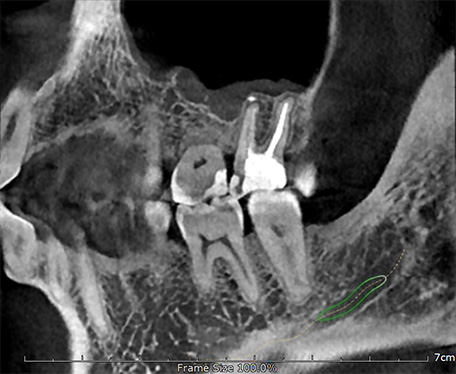

70 мкм в Эндодонтическом режиме 3,5×4 см

Высокотехнологичный детектор с самым высоким разрешением в классе – 70 мкм. Позволяет различить даже самые мелкие анатомические образования и облегчит постановку диагноза в сложных случаях. А вместе с применением алгоритма SMARF инородные тела из металла не испортят качество снимков.

Алгоритм уменьшения вторичного излучения от металлов

Умная Функция Уменьшения Артефактов от Металла (Smart Metal Artifact Reduction Function) – позволяет минимизировать артефакты от вторичного излучения металлов и получить необходимую диагностическую информацию для постановки корректного диагноза, а также планирования и контроля проведенного лечения.